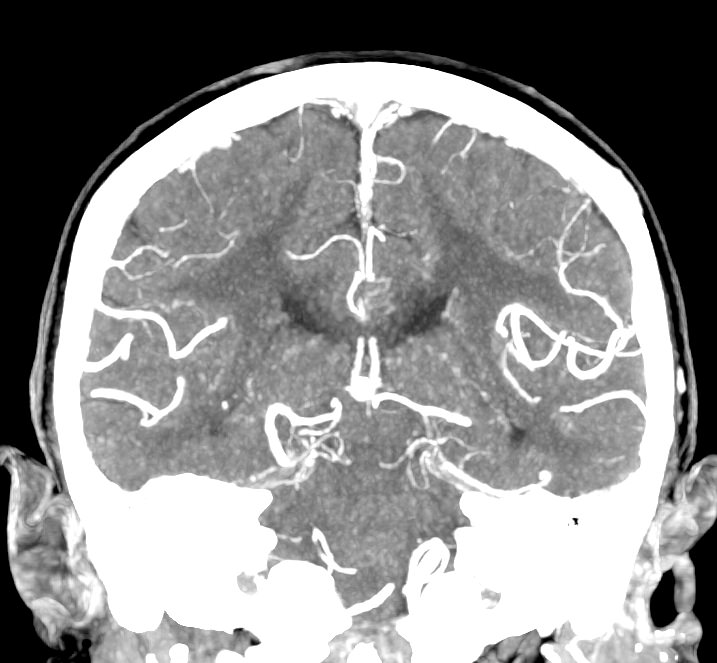

Мультиспиральная компьютерная томография головного мозга относится к лучевым методам исследования и основана на использовании проникающей способности рентгеновских лучей, которые в различной степени поглощаются органами и тканями. Степень поглощения зависит от плотности анатомических структур, благодаря чему можно получить подробные изображения внутренних органов. Во время исследования трубка томографа вращается вокруг пациента и производит снимки поперечного сечения, что позволяет детально визуализировать кости черепа и все структуры головного мозга.

Для улучшения видимости внутричерепных структур применяется методика внутривенного болюсного контрастирования. Во время проведения КТ пациенту в вену вводится йодсодержащее контрастное вещество. Контраст с током крови попадает в патологически измененные участки ткани и очаги, что на снимках придает им яркие отличительные признаки по сравнению с окружающими здоровыми тканями. Контрастирование, в первую очередь, помогает в диагностике опухолевых процессов на ранних стадиях, когда лечение может дать наилучший результат.

В наших медицинских центрах КТ головного мозга с контрастированием проводится на новейших мультиспиральных компьютерных томографах экспертного уровня TOSHIBA AQUILION в различных модификациях. Аппараты снабжены увеличенным количеством сверхчувствительных детекторов, что позволяет при сканировании выполнять множество срезов поперечного сечения с минимальной толщиной среза от 0,5 мм. В результате получаются изображения исследуемой зоны в мельчайших подробностях, которые затем с помощью инновационных цифровых приложений преобразуются в трехмерные пространственные модели головного мозга для более точной диагностики. Помимо высокого качества изображений увеличенное количество детекторов обеспечивает быстроту выполнения сканирования, что значительно снижает уровень рентгеновского облучения для пациента во время обследования.

КТ кроме ткани мозга позволяет оценить состояние костей черепа, при прорастании опухоли выявить участки истончения и структурные изменения костной ткани. Учитывая быстроту выполнения, КТ чаще применяют в экстренных ситуациях, например, для оценки травматических повреждений, дифференциальной диагностики ишемических и геморрагических инсультов, выявления внутричерепных гематом, абсцессов, кистозных образований.